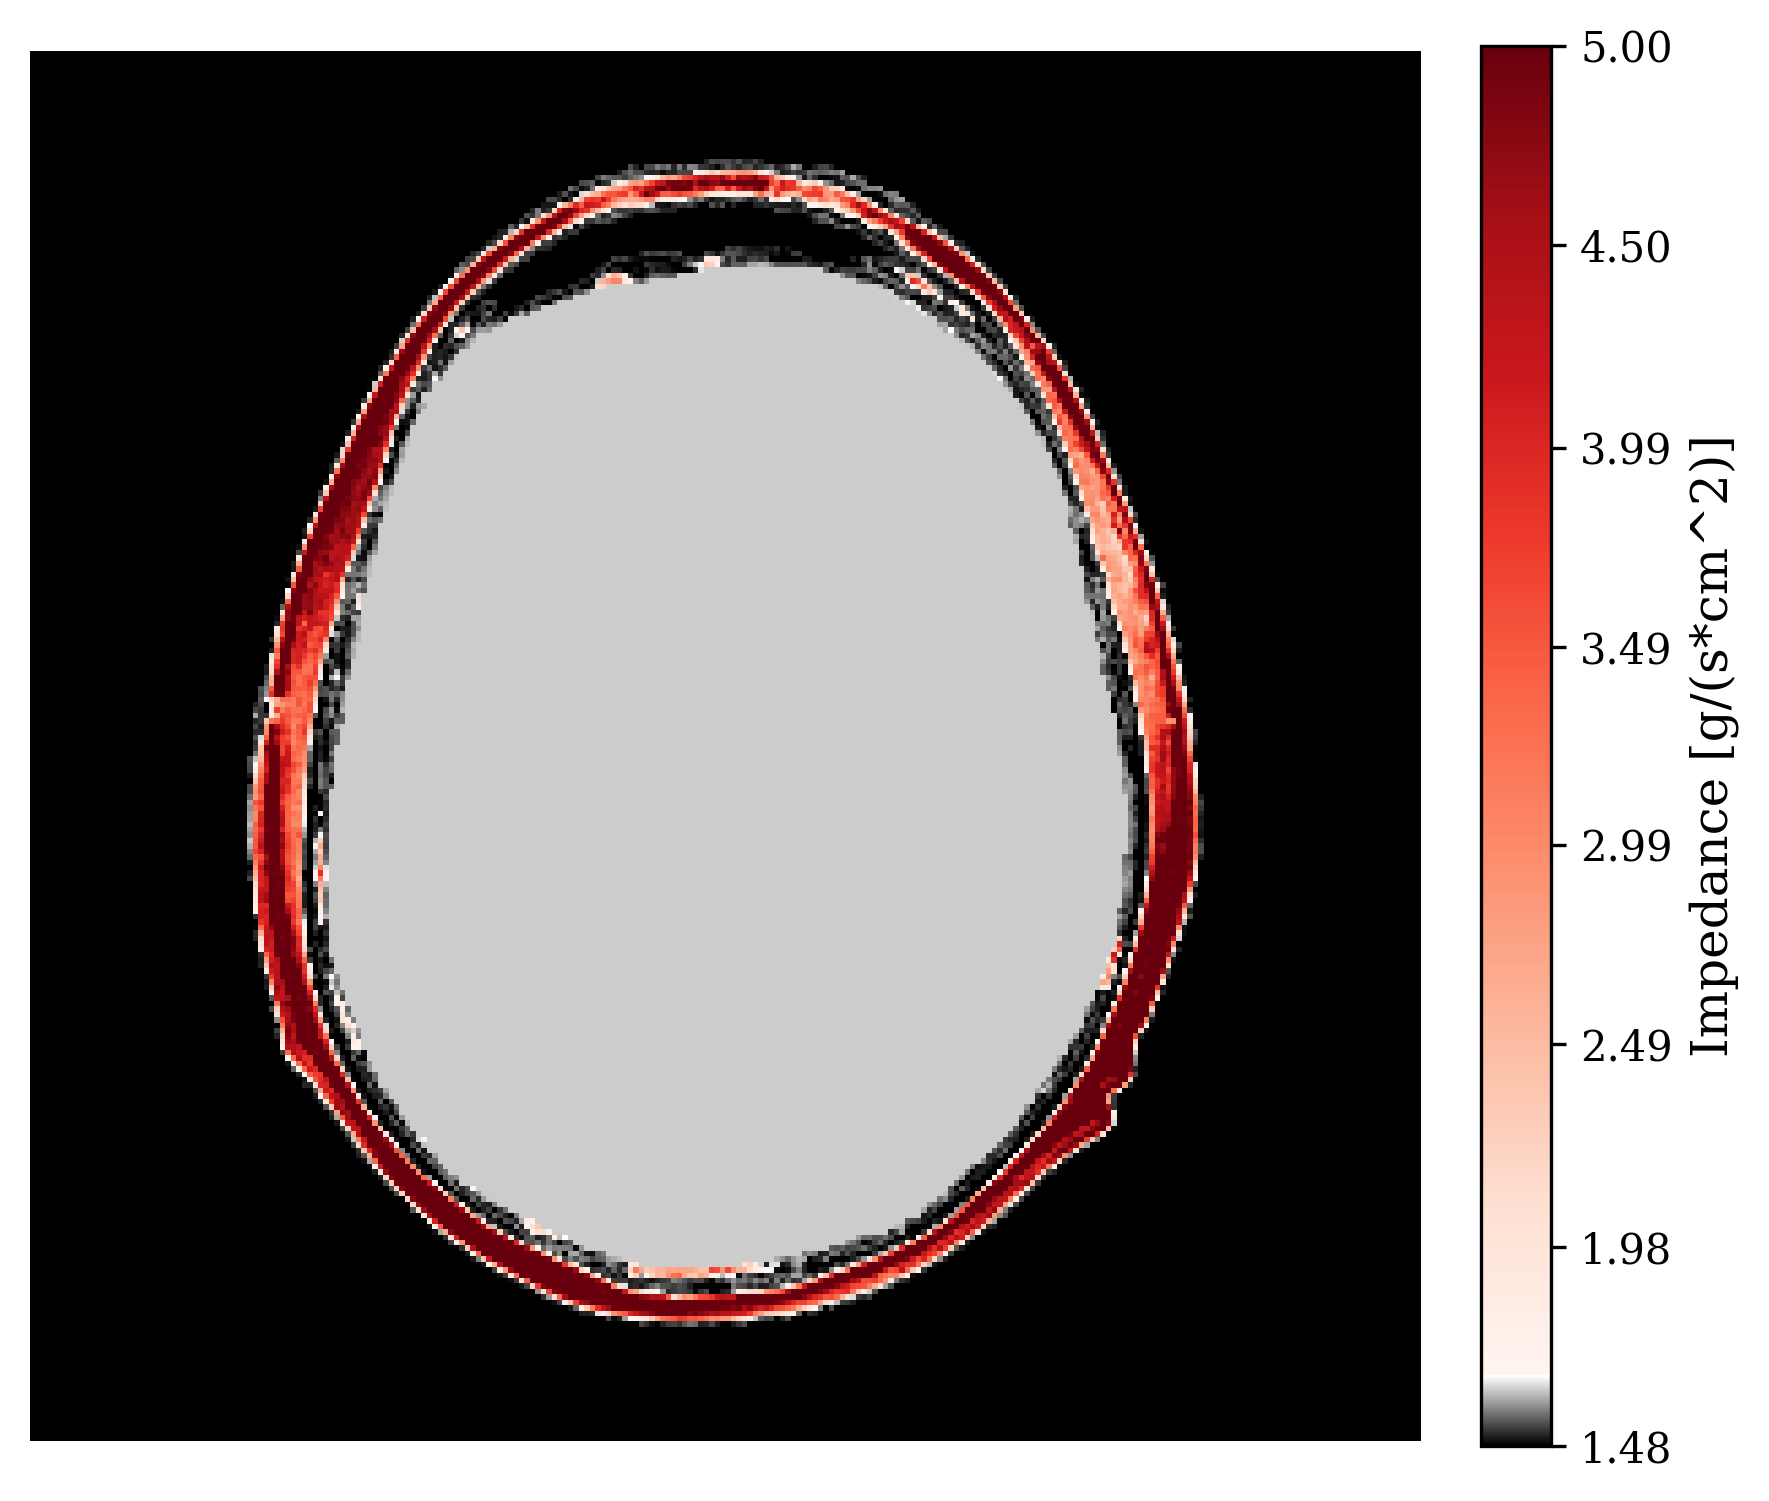

with being the full observation over sources. To account for errors in the measurements, an additive noise term is included as . Typical 3D hardware setups have sources and for our 2D simulation we use up to sources. This makes the full observation . Figure 2 shows data of a single source experiment with the acoustic impedance shown in Figure 2. In our setup, we model transducer receivers around the skull, of which also act as sources. They record for time steps. Given observed transcranial ultrasound data, , our aim is to invert for internal structures . We solve this inverse problem in a Bayesian framework so uncertainty due to incomplete measurements, modeling errors, and noise, can be quantified systematically.

where is a starting point at which the gradient is calculated. Note, \equationrefeq:summ-data involves evaluating the forward physical model and its Jacobian adjoint . Thus this summary is informed by the physics (domain knowledge). As a result, the summarized data lives in the reduced image space (reduction factor of about ). According to Fluri et al. (2021), the informativeness of this summary statistic also implies that thus we propose to use the same conditional distribution learning objective as \equationrefeq:train-cond but replace the data with the summary . See Algorithm 1 in the Appendix for our full training process. The technical assumptions for the informativeness of this summary statistic are discussed in Appendix 4.5 alongside studies to understand the effect of deviations from the assumptions. One of the assumptions is that the starting point needs to be carefully chosen as it will affect how informative the summary statistic will be. For our application, is the acoustically correct model of the skull bone and a constant acoustic model inside the skull since the soft tissues inside the skull are the clinically relevant structures we care to image. Inclusion of the skull is needed so that the physical operators create meaningful results that inform the posterior. In practice, acoustic values of skull bone can be calculated from CT scans Aubry et al. (2003). See Figure 2 for an example of and Figure 2 for the physics-informed summary it creates.